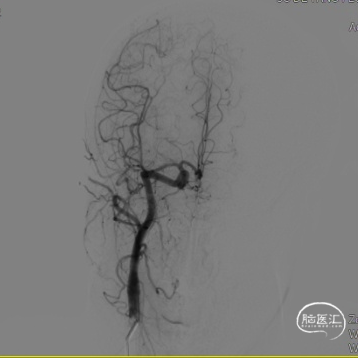

左侧颈内动脉造影提示:左侧颈内动脉C4段多发动脉瘤。大小分别为3.5mm*2.5mm、2.5mm*2.5mm,余各血管及其分支血管走形正常,动脉期、毛细血管期、静脉期均未见异常血管病变,脑循环时间正常。

2. 术前全脑血管造影提示:左侧颈内动脉C4段多发动脉瘤;

(A)

(B)

(C)

A:支架到位前造影确定动脉瘤位置以及拟释放支架位置;B:支架到位;C:支架到位后再次确定支架与动脉瘤位置关系。